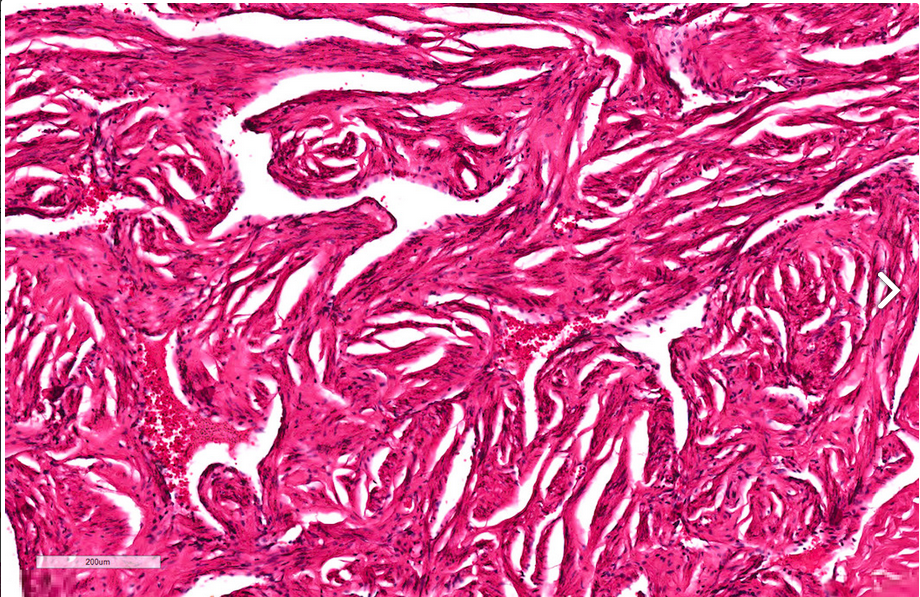

Corpora cavernosa

High power view of interanastamosed slit-like vascular spaces with thin muscular walls.

Complex tridimeensional network of trabeculae.

Vessel walls: thick bundles of smooth muscle. The vascular structures of the corpora cavernosa are thicker adn more complex when compared with those of the corpus spongiosum.